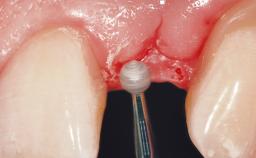

A 42-year-old female patient was referred to our clinic at the School of Dentistry of the University of São Paulo in November 2004, presenting a deficient restoration in the upper left central incisor. The clinical examination revealed no gingival retraction or any signs of gingival inflammation and, therefore, previous periodontal treatment was not considered. The patient presented a high lip line at full smile and a thin tissue biotype. This combination characterized a high-risk situation from an anatomic point of view, which required careful preoperative planning and cautious surgical execution.

Placement Protocol Immediate implant placement

Tooth Site Maxillary incisor or canine

Socket Morphology Single-root socket